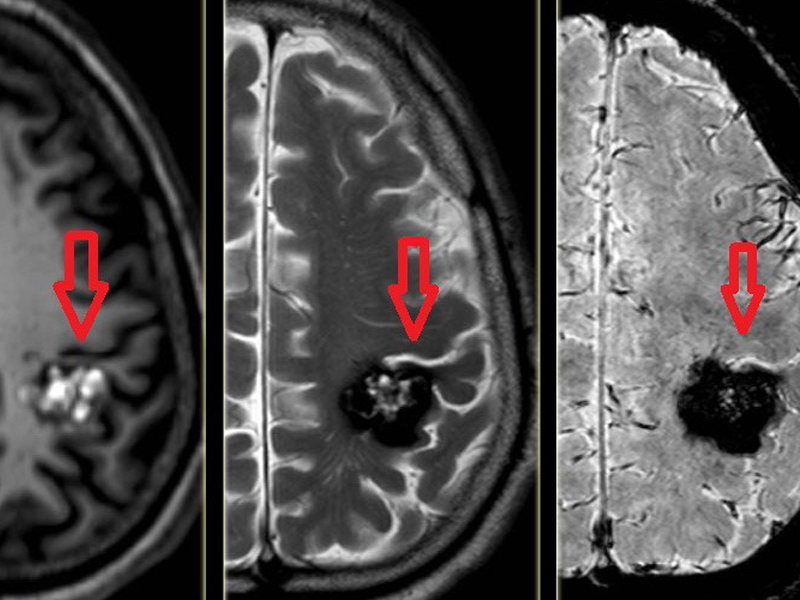

Bệnh nhân được bệnh viện tuyến dưới chuyển ra trong tình trạng ý thức chậm, liệt hoàn toàn nửa người phải. Bệnh nhân ngay lập tức được chụp phim cắt lớp vi tính não và mạch não, kết quả phát hiện chảy máu não vùng thái dương, tràn máu vào trong não thất.

Bệnh nhân không có tiền sử bệnh lý tăng huyết áp và rối loạn chức năng đông máu. Tuy nhiên dựa vào hình thái và vị trí chảy máu não, bác sĩ xác định bệnh nhân có dị dạng thông động tĩnh mạch não, là nguyên nhân gây vỡ mạch máu não dẫn tới đột quỵ.

Hình ảnh chảy máu não vùng thái dương của nữ bệnh nhân